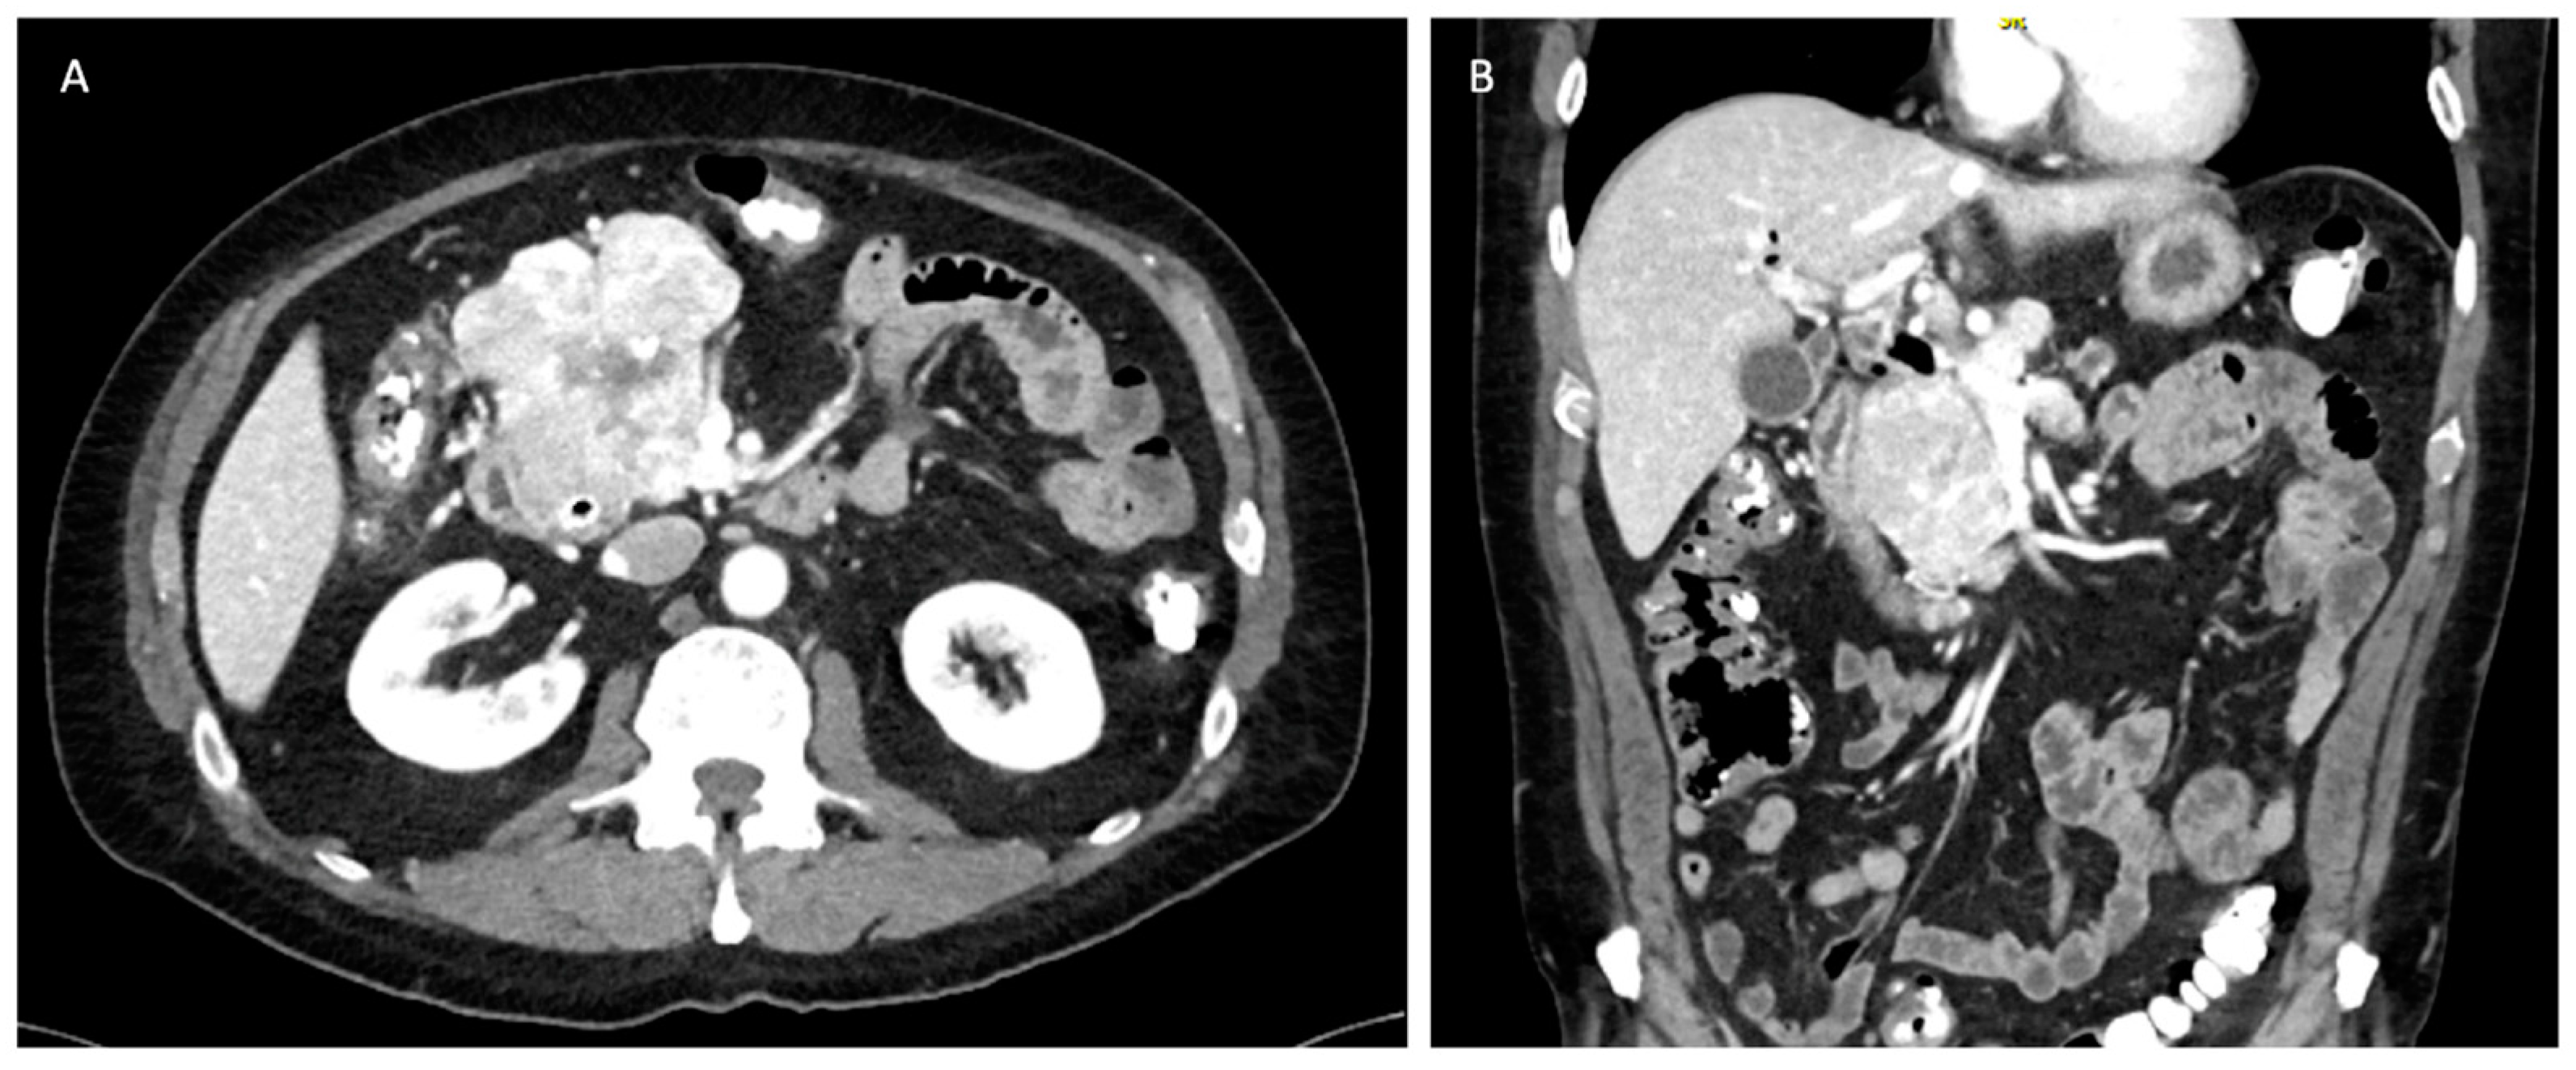

5.3.5. Tumors with Liver Metastasis

PNETs most commonly metastasize to the liver, bone, and lung. Liver metastases have been associated with worse overall survival [47]. However, curative resection can be pursued for isolated metastasis with some improvement in overall survival if the primary lesion can be resected as well [48]. The pattern of liver metastasis is usually multiple small tumors involving both hepatic lobes (Figure 6) [49]. The NANETS guidelines did not reach a consensus on the utility of cytoreduction in this setting, and the evidence supporting resection remains scarce. However, cytoreduction should be considered if patients are symptomatic and debulking is able to improve their quality of life [11]. Synchronous surgical resection of hepatic metastases and primary tumor can be performed with acceptable low mortality in selected patients [49]. Single-staged pancreaticoduodenectomy and major hepatectomy is discouraged due to its associated morbidity and mortality rates [13]. Isolated liver metastasis from neuroendocrine tumors is currently an acceptable indication for liver transplantation. The Milan or UCSF criteria should be utilized to select these patients appropriately [50]. The 5-year overall survival ranges from 36 to 90%; however, the data is not uniform and is prone to selection bias due to the retrospective nature of published studies [51,52,53].

5.3.6. Role of Liver-Directed Therapies for Liver Metastasis

Metastatic involvement of the liver significantly impacts patients’ quality of life, often leading to carcinoid syndrome, biliary obstruction, liver insufficiency, and abdominal pain (Figure 6) [54,55]. For patients experiencing symptoms but deemed not to be surgical candidates, various liver-directed therapies offer viable treatment options. These encompass percutaneous ablation techniques such as laser ablation (LA), radiofrequency ablation (RFA), microwave ablation (MWA), and irreversible electroporation (IRE). Additionally, endovascular treatments, including transarterial embolization (TAE), transarterial chemoembolization (TACE), and peptide receptor radionuclide therapy (PRRT), are also effective alternatives [51,56,57,58,59]. These modalities can be used alone or in combination with each other. In general, ablative techniques are effective and safe for oligometastatic disease. For diffuse disease with involvement of more than 75% of the liver, endovascular approaches and PRRT represent better alternatives, although they are limited by their availability at specialized centers [59].

Figure 6. Unresectable liver metastases from pancreatic neuroendocrine tumor. (A) Axial view. (B) Coronal view.